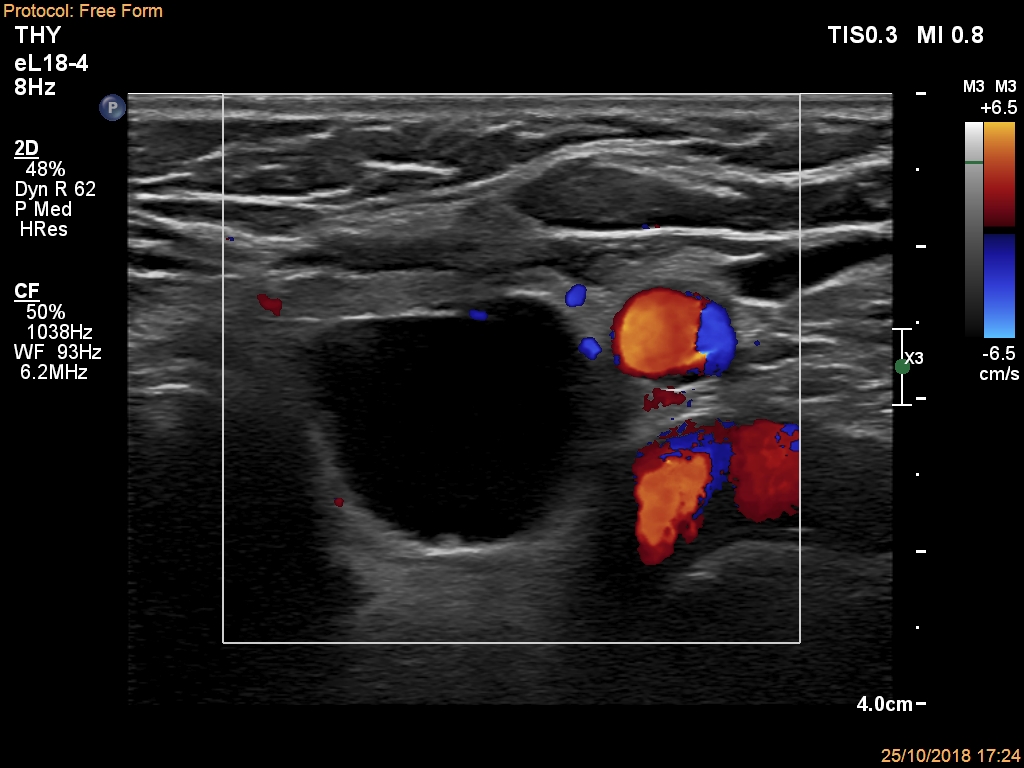

Lower part of the left lobe, transverse scan, color Doppler mode. The nodule is avascular.